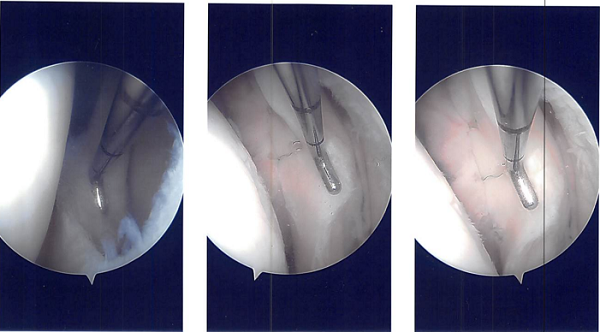

Arthroscopic surgery was performed. Lateral anterior portal was made for arthroscopic viewing. The scope was entered and the camera was entered. The camera showed a tear of the posterior horn and brought the posterior body of the lateral meniscus around the popliteal hiatus at its periphery.

The tear was repairable and I decided to repair it. There was a grade 2 to grade 3 chondral lesion over the patella as well as lateral condyle of the femur. Chondroplasty was performed. The meniscal rasp was used to prepare the capsular as well as the meniscal attachment.

A plane was made between the popliteus and the gastrocnemius with the vessels behind. Sims speculum was used to retract the vessels posteriorly. Another scope was reintroduced on the lateral border and all-inside repair was done using FasT-Fix with a Nephew curved all-inside implant and sutures.